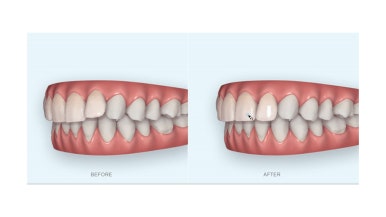

초진 시 얼굴 모습입니다.

전반적으로 모두 양호합니다. 입이 편안하게 다물어지는 느낌, 옆라인, 심지어는 중앙선까지 양호합니다.

단 하나, 작은 앞니 하나가 톡 튀어나와 있는 부분이 미적으로 좋지 못한데요.